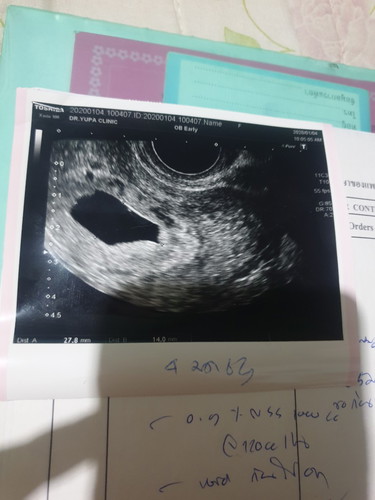

ท้องลม

เรื่องที่เราไม่อยากให้เกิด ตอนนี้มันเกิดขึ้นกับเรา เสียใจมาก ไม่คิดว่าจะเกิดกับเรา พรุ่งนี้หมอนัดขูดมดลูกแล้ว ยังทำใจไม่ได้ ยังเชื่อว่าปาฏิหาริย์มีจริง แต่เราต้องยอมรับในความเป็นจริง ตอนนี้ทั้งเรา ทั้งแฟน สภาพจิตใจแย่พอๆกัน พูดไม่ออกกันเลย ?

ตอนเราท้องครั้งแรกน้องมาแบบไม่ทันตั้งตัว ตอนนั้นไปหาหมอตอน5week หมอผ่านซาวด์ผ่านหน้าท้องเจอแต่ถุงการตั้งครรภ์ หมอเลยนัดต่ออีกตอน8week แต่ในระหว่างนั้นมีเลือดออกกะปริบกะปรอยตลอด หมาจ่ายยากันแท้งให้กินจนสัปดาห์ที่8หมอก็ซาวด์อีกครั้งแต่ผ่านทางช่องคลอดหมอพบตัวแต่น้องไม่มีหัวใจและไม่มีการเจริญเติบโต และที่สำคัญหมอพบว่าเราตั้งครรภ์แฝด ตอนนั้นหมอก็ค่อนข้างมั่นใจแล้วว่าเราต้องเอาออก แต่คุณหมอก็หันมาถามเราว่าจะลองให้โอกาศเขาไหม ตอนนั้นเราหูดับไปหมดแล้วทั้งเสียใจทั้งงงไปหมด เรากับสามีเลยตัดสินใจรอจนสัปดาห์ที่9week หมอซาวด์อีกครั้งสรุปหมอบอกน้องไม่เจริญเติบโตจริงๆ หมอส่งเราเข้าแอดมิดที่ รพ.ทำการเหน็บยาให้หลุดออกมา แต่ของเราหลุดหมด ไม่ต้องขูดมดลูก ตอนนี้ผ่านมา 6 เดือนน้องมาแล้วคะแค่6weekซาวด์ครั้งแรกก็เจอหัวใจแล้ว อยากเป็นกำลังใจให้คุณแม่นะคะ เดี๋ยวน้องก็มาใหม่คะ เราคิดเสียว่าเขาไม่สมบูรณ์ให้เขาเกิดมาสมบูรณ์ดีกว่าต้องเกิดมาแล้วไม่สมบูรณ์นะคะ#จากคุณแม่ที่เคยชีวิตเกือบพังแต่ครอบครัวประคับประคองและกอบเราขึ้นมา😊😊

ของพี่เป็นตัวอ่อนแล้วค่ะ ซาวด์ตอน 8w ไม่มีหัวใจ